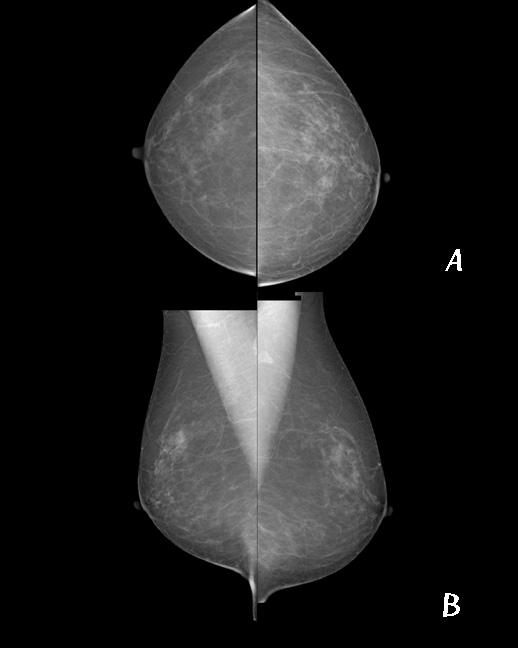

검사방법

장비위에 유방을 놓고 최대한 유방이 포함되게 자세를 잡은 뒤 충분히 압박하여 검사합니다.

기본적으로는 한쪽 유방에 A : 상 하 방향(up-and down view, Cranial-caudal;CC), B : 내 외 방향(side-to-side view, medial-lateral-oblique;MLO)으로 각 2번씩 총 4번 촬영 합니다. 검사 시 압박에 의한 통증으로 인해 불편함이 있을 수 있으나 최대한 움직이지 않으셔야 움직임으로 인한 재촬영을 피할 수 있습니다.